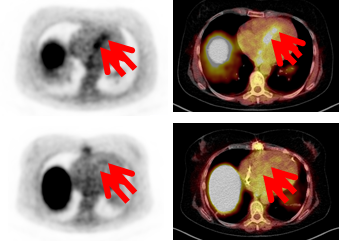

Der Grund, warum man beim Patienten so wenig über die Heilung nach Schädigung des Herzens weiß, liegt daran, dass es keine einfachen Verfahren gibt, die relevanten physiologischen Vorgänge zu erfassen. Blutwerte sind zu ungenau, Biopsien – also die Entnahme von kleinen Gewebestücken – sind für die Patienten zu belastend und es kann auch sein, dass man nicht das betroffene Areal findet oder trifft. Den Würzburger Medizinern Dr. Reiter und Dr. Lapa aus der Forschungsgruppe um Professor Bauer ist es jedoch gelungen, die Entzündungsvorgänge im menschlichen Herzen direkt darzustellen: Ihre Verfahren und Ergebnisse publizierten sie in den international renommierten Fachmagazinen International Journal of Car-diology und dem European Heart Journal. Die Forscher nutzen nuklearmedizinische Verfahren in Kombination mit der Kernspintomographie, um die Zellen und Umbauvorgänge während der Entzündung im Herzen abzu-bilden. „Zunächst musste die Gruppe molekulare Spürsonden entwickeln, die die Entzündungszellen sichtbar machen. Das gelang den Forschern Dr. Li und Prof. Samnick mit einer radiochemischen Methode, bei der molekulare Strukturen auf der Oberfläche von Immunzellen markiert werden. Das Ausmaß der Gewebeschä-digung im Herzen wurde mit der Kernspintomographie dargestellt. Dabei kann man z.B. das Gewebewasser, das bei einer Entzündung vermehrt ist, oder abgestorbene Zellengruppen sehen. Durch die Kombination der nuklearmedizinischen Technik mit der Kernspintomographie war es uns letztendlich möglich, erstmals bei Patienten das Ausmaß der Schädigung des Herzmuskels nach einem Infarkt darzustellen“, erklärt Prof. Bauer.